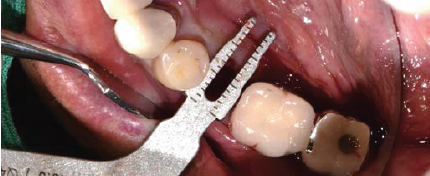

Volume Up Gauge를 Implant 식립부위에 위치하여 Healing Abutment 직경 확인

Volume Up Gauge의 홈에 맞춰 Point Drill의 위치 파악

제조사의 식립순서에 맞춰 Drilling 후 Fixture 식립

Fixture 식립